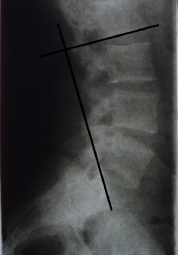

Hier sind meine Roentgenbilder, was sagt ihr dazu?

Eins noch - Ihr schreibt der Arzt muss ausmessen wieviel grad dieses Hohlkreuz hat, kann ich das nicht auch irgendwie selbst hinkriegen?

Ist das nun ein Scheuermann oder woher kommen diese Verknöcherungen?